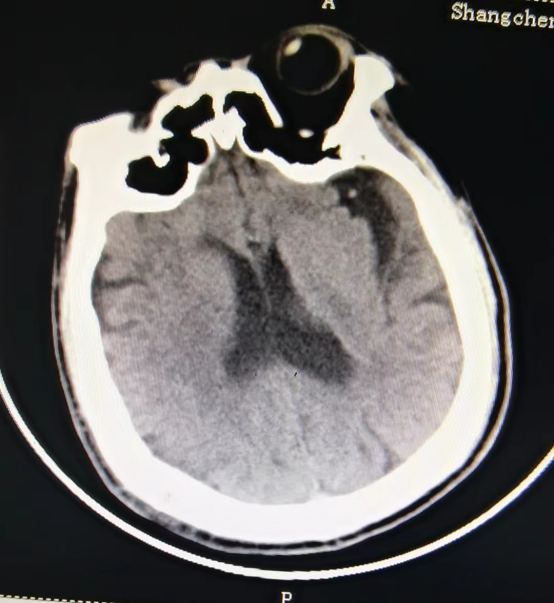

近日,55岁的冯先生突发急性脑梗死,我院卒中中心启动绿色通道,给予静脉溶栓桥接取栓治疗,成功打通堵塞的“生命管道”,患者转危为安,术后恢复良好,避免了“一人中风,全家瘫痪”的悲剧。